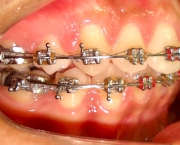

* Os aparelhos, feitos para alinhar os dentes, podem também contribuir para o aparecimento das sensibilidades nos dentes.